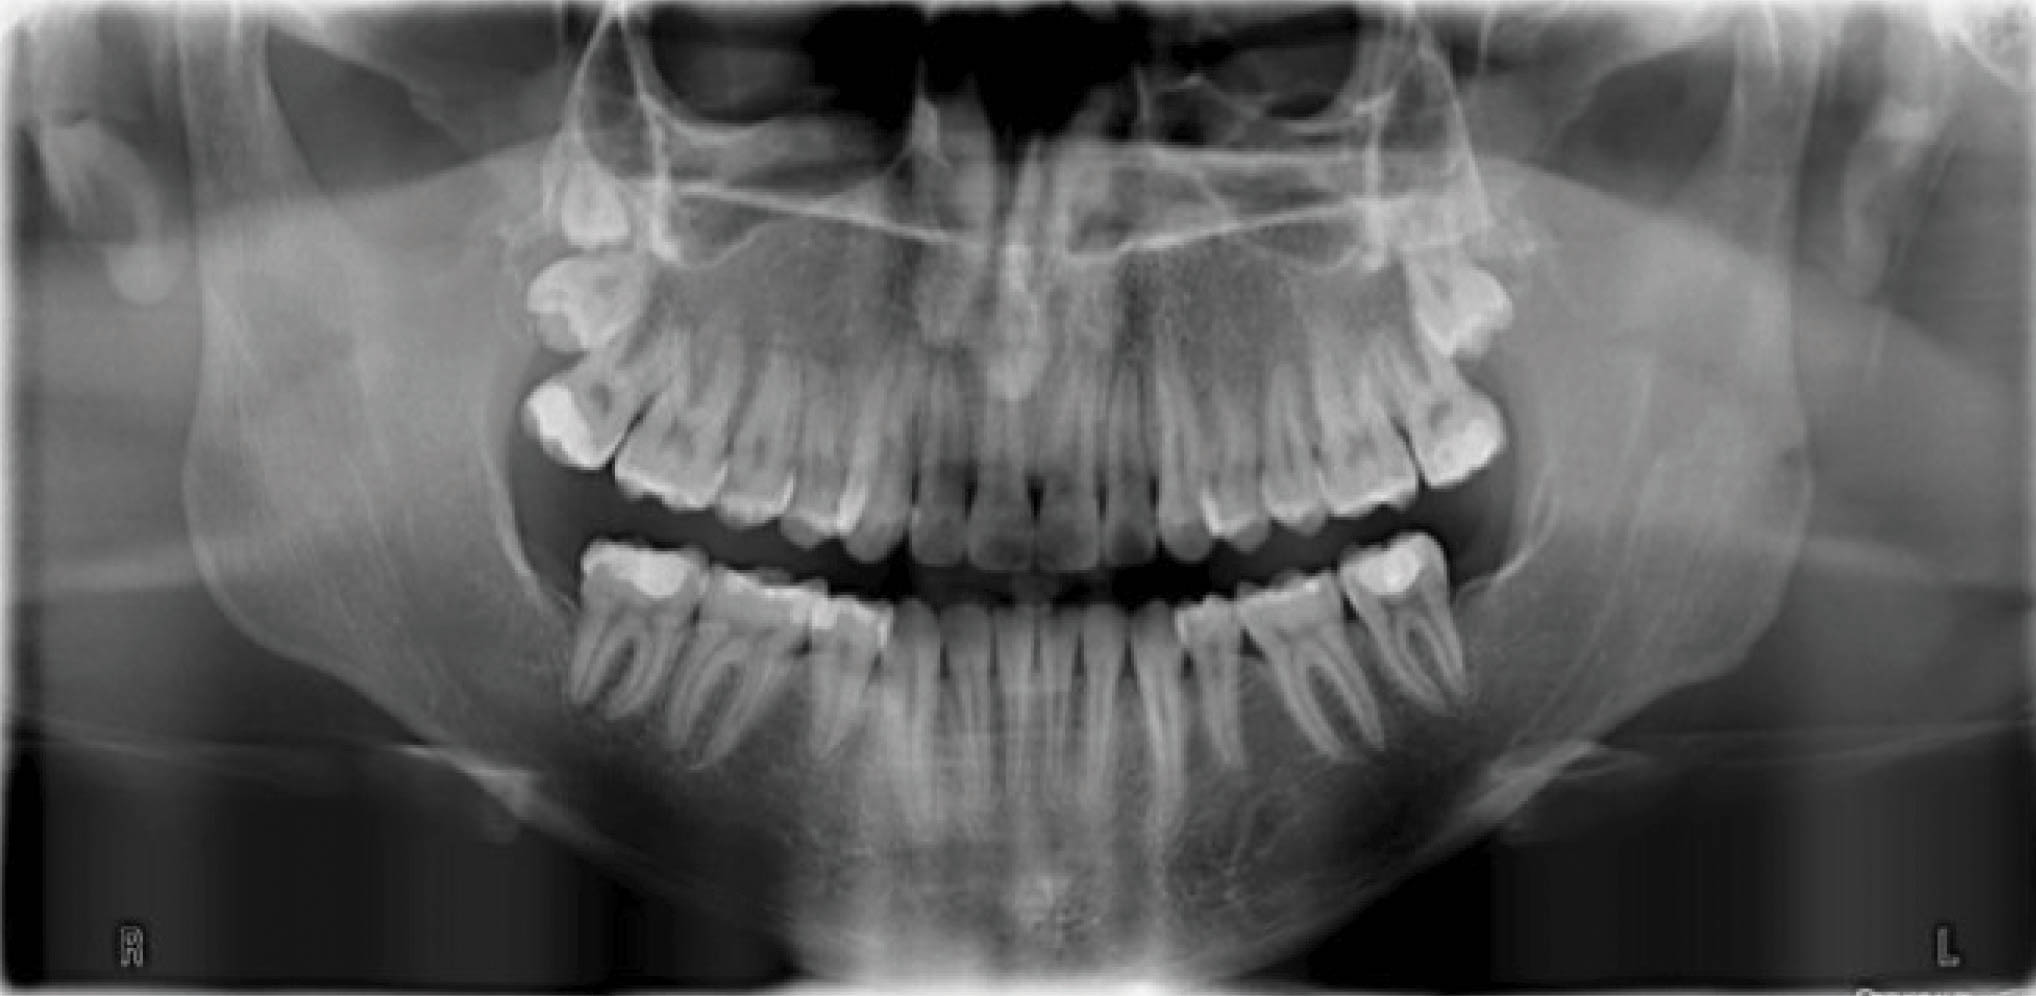

بیمار بعدی یک دختر ۱۶ ساله ClII/1 با اوربایت نرمال و اورجت زیاد است. کرادینگ مختصر دو فک دارد، قوس بالا تنگ، و پروفایل او طبیعی است (شکل 83-۶ الی 85-۶). در این بیمار از الاستیک کلاسII استفاده شده است. الگو اسکلتی طبیعی، رادیوگرافی لترال سفالومتری نشان دهنده دندانهای قدامی پروترود شده بالا با الگو طبیعی اسکلتی میباشد. رادیوگرافی OPG طبیعی است. قسمت بعُد افقی چک لیست را به این نحوه پر کردیم:

شکل 83-6

شکل 84-6

شکل 85-6